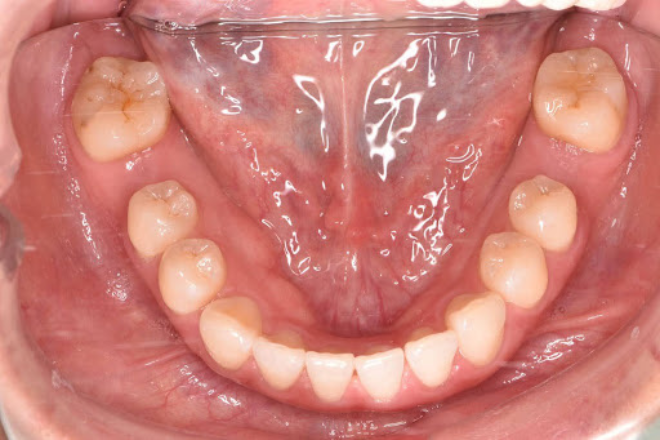

以下は、赤坂さくら歯科クリニックのインプラントでしっかり噛めるようになった症例です。

下顎左右6番を虫歯で失われていたため、サクライナーというオリジナルマウスピース矯正で隙間を埋めて2本のインプラントを埋入しました。

Before